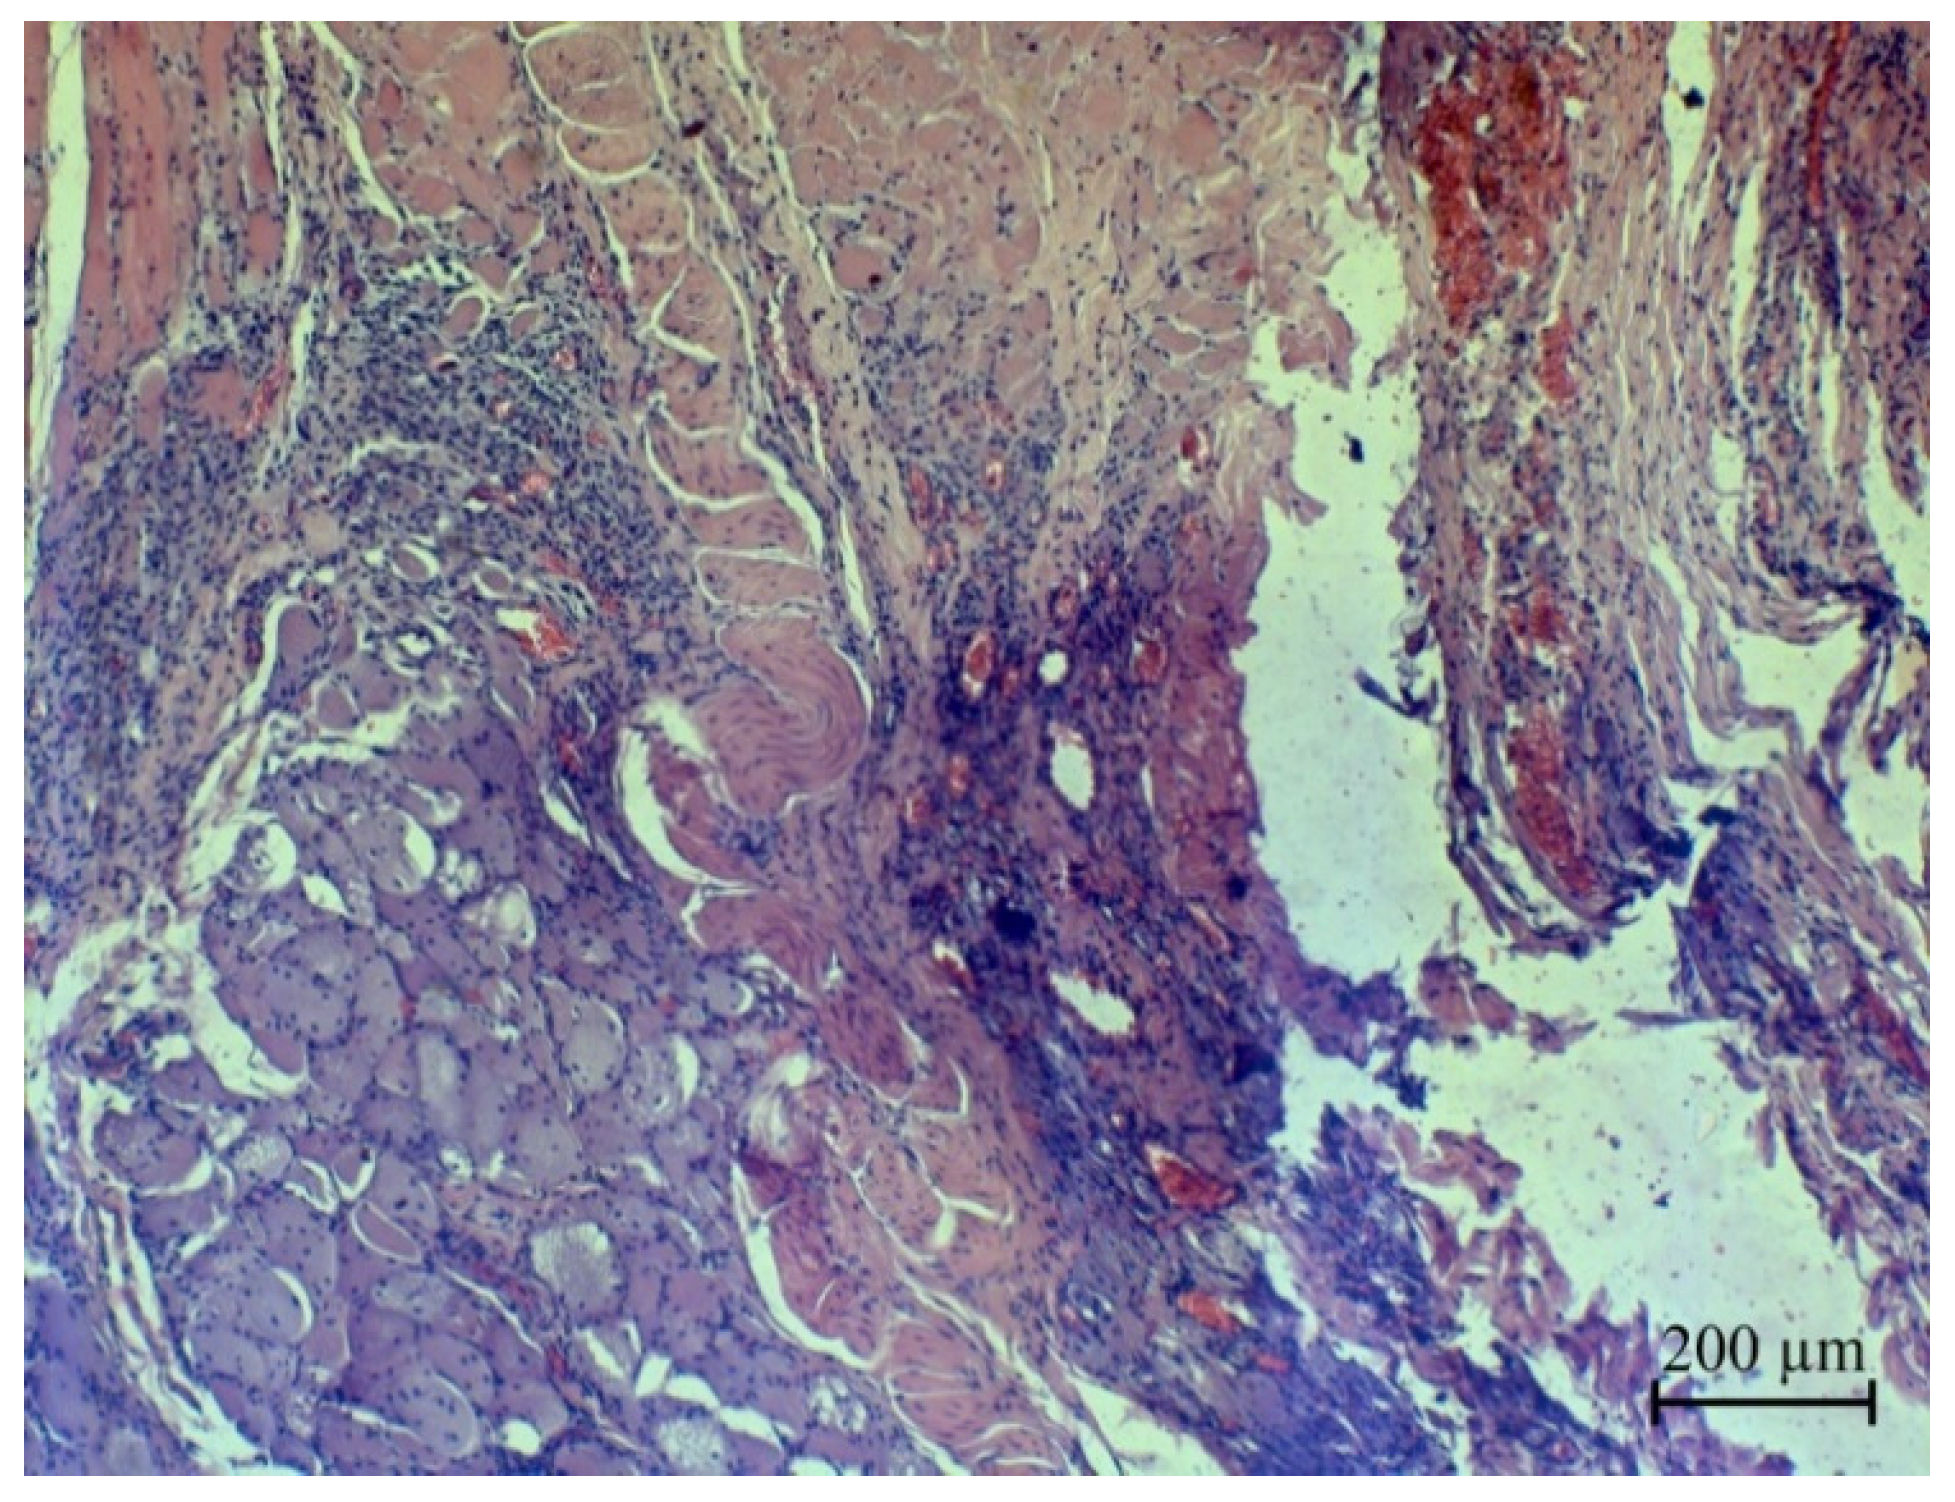

3.4. Investigation of Ag NPs and the Oxidized Ag NPs as a Covering Component of Suture Materials

- Rzhepakovsky, I.; Siddiqui, S.A.; Avanesyan, S.; Benlidayi, M.; Dhingra, K.; Dolgalev, A.; Enukashvily, N.; Fritsch, T.; Heinz, V.; Kochergin, S.; et al. Anti-arthritic effect of chicken embryo tissue hydrolyzate against adjuvant arthritis in rats (X-ray microtomographic and histopathological analysis). Food Sci. Nutr. 2021, 9, 5648–5669. [Google Scholar] [CrossRef]